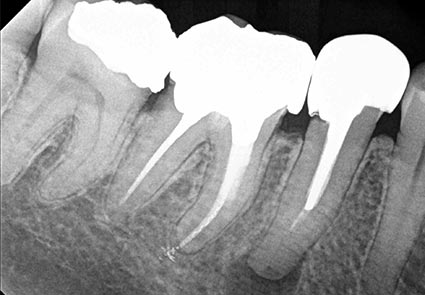

GENDEX GXS-700

Utilizing the latest sensor technology, the GXS-700 system delivers

real-time images of truly amazing clarity and detail — greatly supporting

diagnosis and treatment. Easily capture high definition

images of both horizontal and vertical bitewings, as well as effortlessly

capture challenging areas such as third molars and long-rooted canines.

WHAT IS THE ADVANTAGE OF DIGITAL RADIOGRAPHY?

First and foremost, digital radiography reduces my patient’s exposure to radiation—usually 70 to 80 percent. Many patients are very relieved that digital radiology significantly lowers the amount of radiation they will receive.

In addition, there is no chemical processing of the x-rays, eliminating the inconvenience and environmental impact associated with disposal of conventional film developers.

Thirdly, digital X-rays facilitate communication with patients as well as other practitioners. The digital images are immediately available to view. Using current technology, it is very easy to enhance, enlarge, or refine the X-ray images. Brightness, color and/or contrast of digital X-rays can be adjusted without re-exposing the patient for another film. Patients are now able to view their X-rays instantaneously on the computer monitor screens located in each operatory.

One of the most useful advantages, is that I can send the digital image to other doctors in a few minutes. Often, while a patient is still seated in the dental chair, I can call other referring doctors to discuss their treatment plan. This can understandably save time for both patients and doctors alike.

Finally, digital X-ray images can be stored in each patient’s database on the computer. This process saves time and allows to easily retrieve this information when necessary.